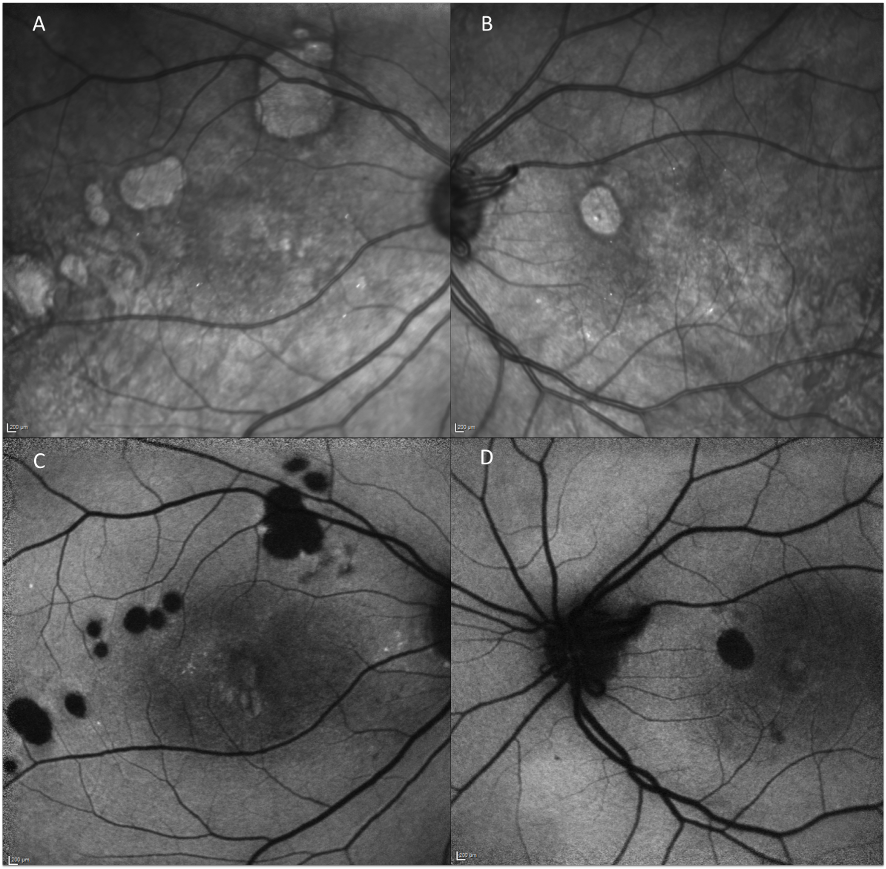

At the initial presentation, the best-corrected visual acuity was 20/100 in the right eye and 20/50 in the left eye (bilateral –3.00 spherical equivalent). The intraocular pressure and slit lamp examination of the anterior segment was unremarkable. Funduscopic examination of the right eye revealed intraretinal hemorrhages, exudates, and a diffuse macular edema. The left retina showed modest intraretinal hemorrhages and microaneurisms at the posterior pole and enlarged arterial calibration (Figure 1 A, B [Fig. 1]). Fundus fluorescein angiography (FFA) revealed an enlarged and clear-cut foveal avascular zone with perifoveal telangiectasia, which was more pronounced in the right eye. Diffuse macular leakage was observed in the late venous phase bilaterally (Figure 1 C, D [Fig. 1]).

Figure 1: Color fundus photography (initial manifestation): radiation maculopathy with enlarged arterial calibration, intraretinal hemorrhages, exudates, microaneurisms, and diffuse macular edema (A, B) Fundus fluorescein angiography (late venous phase): bilateral enlarged and clear-cut foveal avascular zone with perifoveal teleangiectasia and diffuse macular edema (C, D)